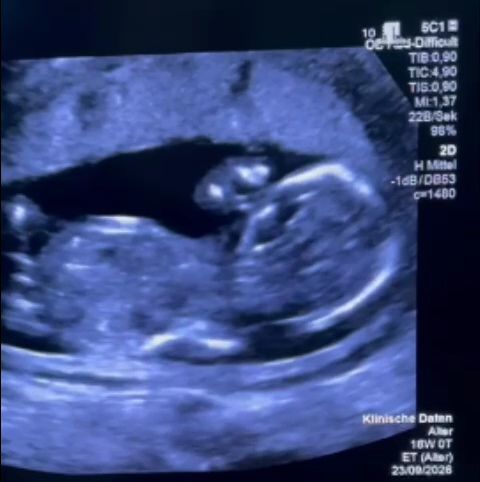

O femeie însărcinată, forţată să se deplaseze în Germania pentru tratament, după ce a trecut printr-o situaţie ”halucinantă” la Spitalul Filantropia din Bucureşti / Ce acuzaţii se aduc – FOTO / VIDEO

Fostul secretar de stat în Ministerul Sănătăţii Monica Althamer, director de program în cadrul Fundaţiei Metropolis, relatează cazul unei femei însărcinate care a aflat, în săptămâna a 12-a, despre o malformaţie minoră, pentru care există tratament. Părinţii au cerut informaţii şi au ales să facă tratamentul necesar la Spitalul Filantropia din Bucureşti. Ajunşi la unitatea medicală, însă, au avut parte de tratament degradant, nu li s-au oferit informaţii şi, în plus, li s-a recomandat să aştepte, deşi un medic german a transmis că procedura este de făcut urgent. Când au cerut eliberarea de documente care să le permită să facă tratamentul gratuit în străinătate au fost, de asemenea, refuzaţi. De Paştele catolic, oamenii au ajuns în Germania, iar procedura a fost făcută a doua zi de către un specialist german, care vorbeşte despre ”o consiliere extrem de slabă” făcută în România.